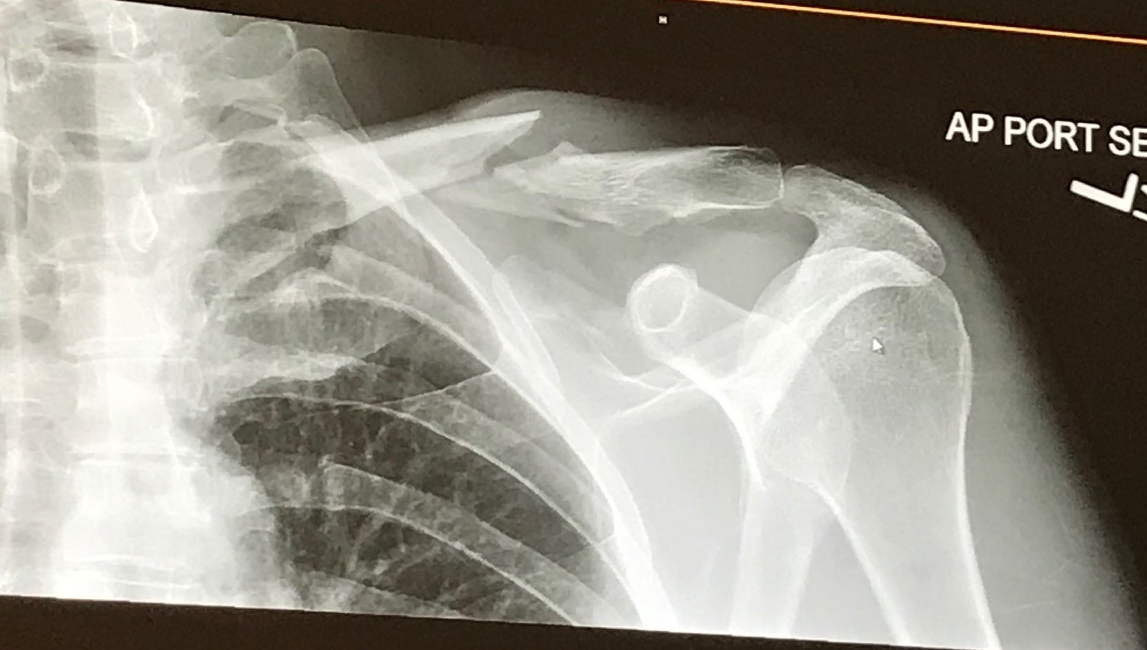

My left clavicle, however, was not so lucky. It was in pieces. As I lay on the pavement staring up at the beautiful big Montana sky, I didn’t know I had broken my clavicle, but I did have the sense that my shoulder was injured pretty badly. I knew my head was okay because I asked if my bike was alright. Turns out it mostly was, but later I would learn that I had a small puncture in my front tube, which caused my front tire to gradually lose air until it failed. Normally, you notice things like this during a ride without something so dramatic happening. It was just an unlucky thing. But I was fortunate to be riding with a group, and also fortunate that I didn’t take out any of them in my fall. They took care of me on the scene, called for help, and got me to the Emergency Room quickly.

I elected to have surgery to put the pieces of my clavicle back together, and I’m glad I did. My surgeon, who did a marvelous job, said most of the time these surgeries take 30 to 40 minutes. Mine took him 90. Yikes. Here’s the before and after: